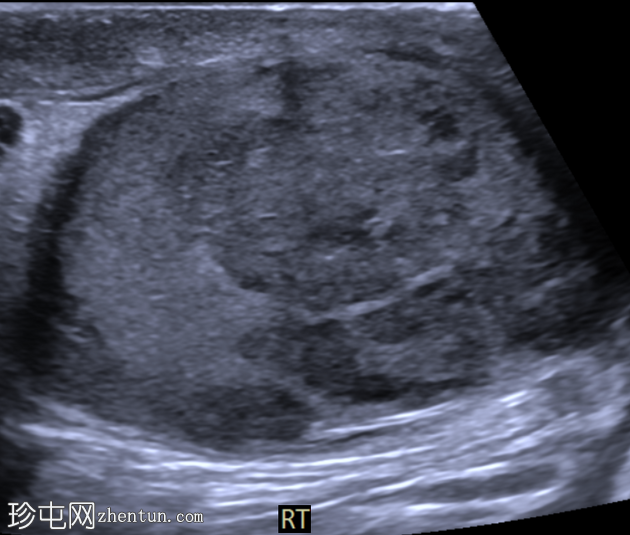

睾丸混合性生殖细胞瘤

右侧睾丸肿块,伴间歇性疼痛4个月。

年龄:30岁

性别:男

超声检查

横切面

右侧睾丸内可见一大小约3.0 x 5.0 cm的异质性分叶状低回声肿块。肿块内未见囊性区域或钙化。彩色多普勒超声检查显示肿块内血流丰富。左侧睾丸正常。